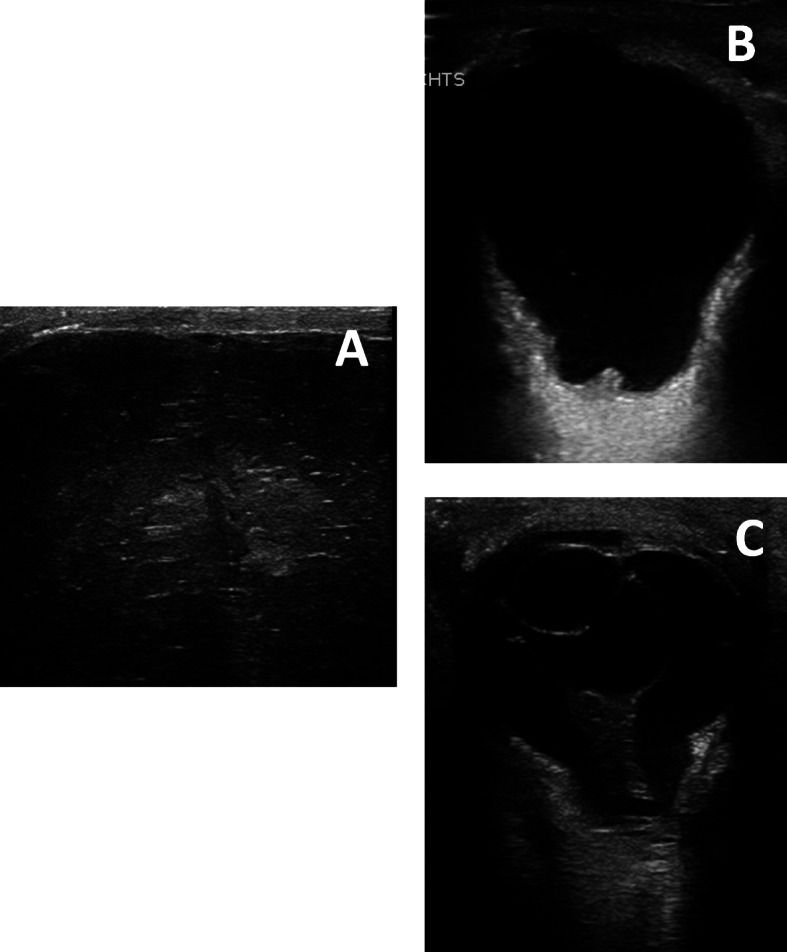

Fig. 4.

Postnatal ultrasound of the brain / eyes; A lissencephaly with polymicrogyria; b staphyloma; c persistent hypoplastic primary vitreous body